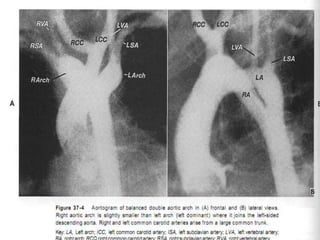

DOUBLE AORTIC ARCH

Two-thirds of these infants, the right-sided (posterior) arch is dominant, and

in one-third, the left-sided (anterior) arch is dominant. Rarely, the arches are

of equal size (balanced arches).

The right arch gives origin to two vessels, the right common carotid and right

subclavian arteries,

The left arch gives origin to the left common carotid and left subclavian

arteries, in that order.

“Four artery sign.” - When the two dorsal subclavian arteries arise directly

from the aorta and not from a brachiocephalic artery.

2 dorsal subclavian arteries and 2 ventral carotid arteries spaced evenly

around the trachea.